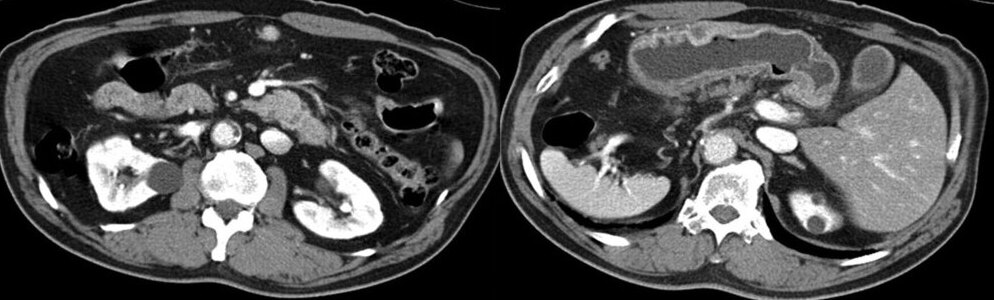

КТ ретроперитонеального фиброза: Изображения и диагностика